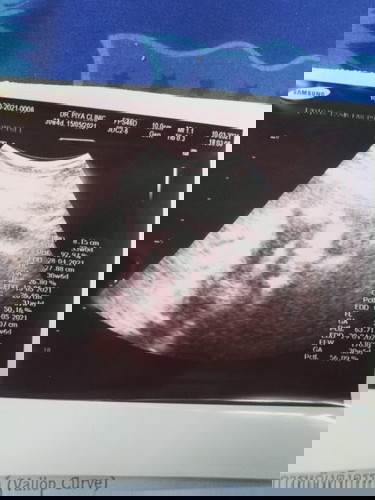

อายุครรภ์30w6d น้ำหนักน้อง1703gแม่บ้านอื่นน้องหนักเท่าใรกันเเล้วค่ะมาเล่าสู่กันฟังจ้า น้องเพศชายกำหนดคลอด15/05/64 #ขอบคุณสำหรับคำตอบค่ะ